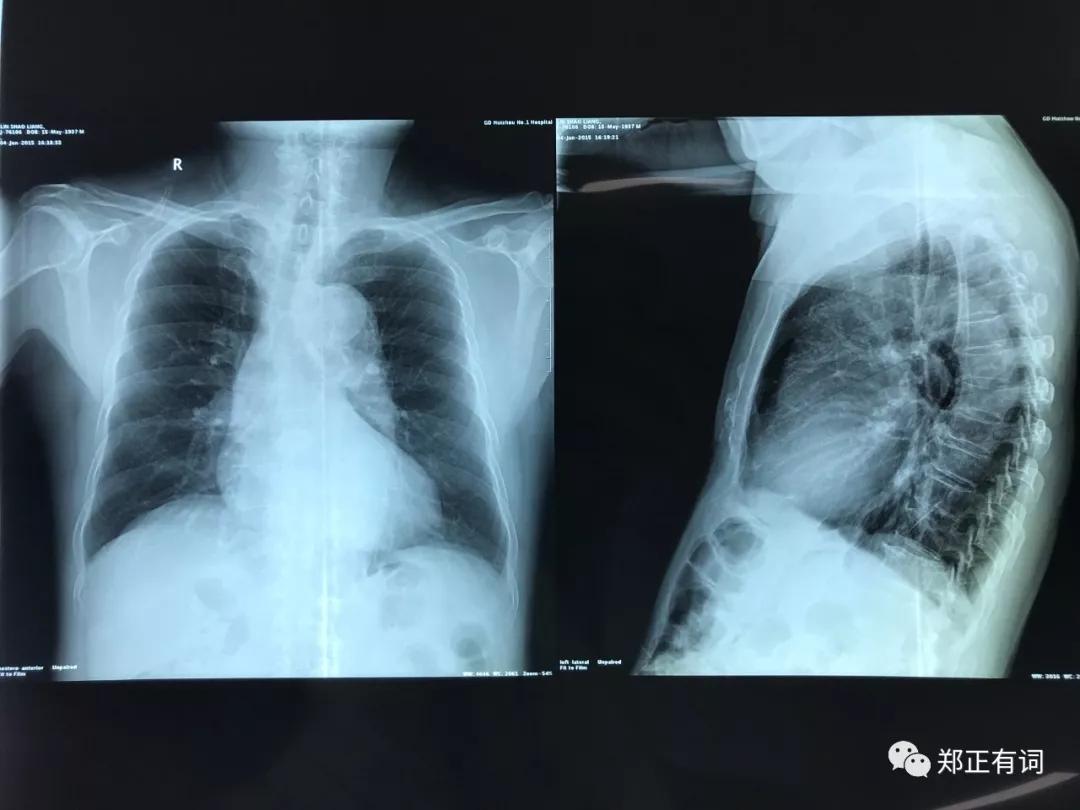

这里分享一个胸片,是这位患者2015年所拍。

这个胸片上,并未发现任何有意义的病变。

但是我猜想,如果正如既往文献所报道,

肿瘤在早期阶段发展较为缓慢,那么有没有一种可能,即当时如果采用CT复查,就能发现一个类似于毛玻璃那样的早期病变呢?

我确实无法回答,

但可以肯定的是,

CT筛查同样适用于高龄患者。

对高龄患者而言,最佳的筛查手段,也是CT。

因为,胸片能发现的问题,往往都是大问题。